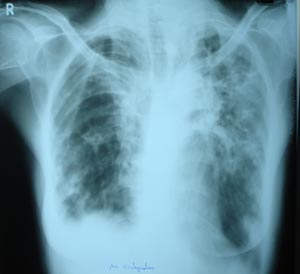

Bilateral extensive fibrosis

A typical fibronodular pattern of reactivation with linear densities. Extending to the hila & atelectasis.